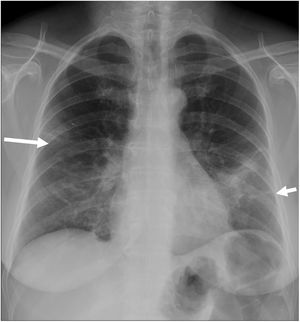

Finally, a third quantification system (8) divided both lungs into 8 lung fields, as reflected in Fig. 2. The involvement of 1–3 fields implied a mild degree; this was deemed moderate when 4–6 fields were involved, and severe if 7 or 8 fields were affected.

Posteroanterior chest X-ray demonstrating division into 8 lung fields by three horizontal lines (quantification system 8). Upper pulmonary field (from vertices to the upper border of the aortic knob), mid-hilar pulmonary field (from aortic knob to hila), mid-paracardiac pulmonary field (from hila to lower third of the cardiac silhouette), lower pulmonary field (from lower third of cardiac silhouette to costophrenic sinuses).